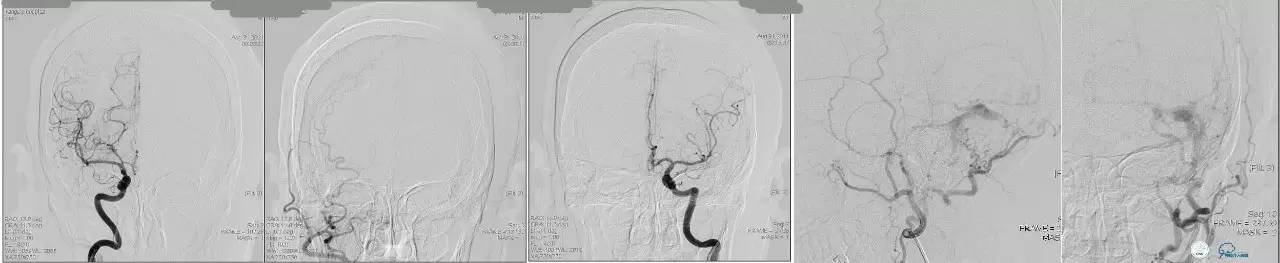

侧窦区DAVF,直接引流入横窦,为保护窦,横窦放入球囊8*80。

最终栓塞结果,窦通畅。

文献中图片,上矢状窦内放置球囊保护。

文献中图片,经颈外动脉栓塞,在椎动脉内放置保护球囊,防止通过脑膜后动脉逆向栓塞椎动脉。

脑膜后动脉供血的小脑幕的瘘。

颈内不参与供血。

大脑后动脉有细小分支供血。

Sceptor球囊无法到达瘘口位置,放在主干内,充盈球囊后把动脉血管床内血液冲洗干净,形成楔入效果。